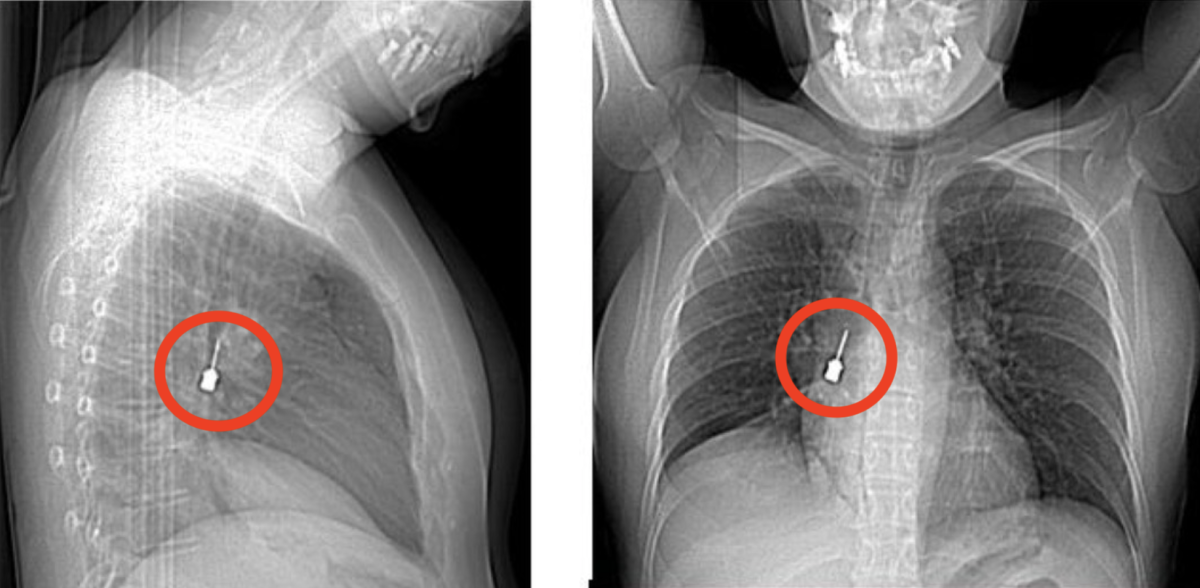

Cacciavite odontoiatrico incastrato nei bronchi di una donna. "È stato inalato per sbaglio"

La paziente è arrivata in ospedale con "tosse e dolore al petto". È stata sottoposta a una delicatissima procedura broncoscopica dalla Chirurgia Toracica e dimessa in ottime condizioni